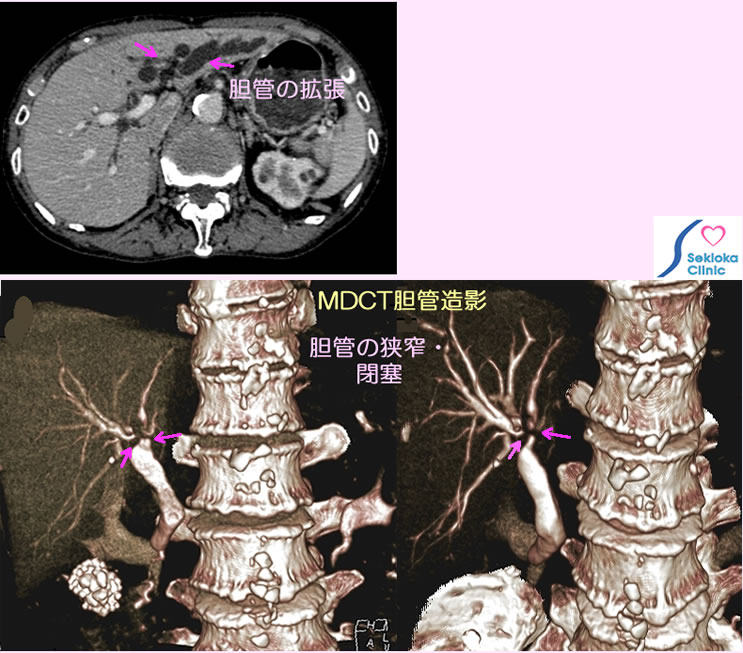

胆管がん

自覚症状なし。黄疸も認めない

肺炎のため胸部CT検査時,偶然、左葉肝内胆管の拡張を認め、原因精査のため腹部造影CT、胆管造影MDCTを行った

本来手術適応であるが 患者さんの意向で保存的治療